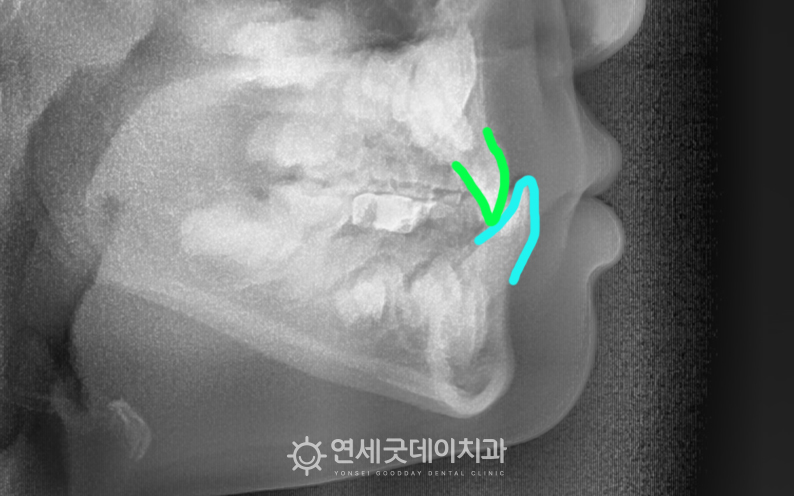

▲ 치료전 엑스레이 (촬영시기 : 2024년 9월)

위 어린이는 턱뼈의 골격적인 문제가 발생하면서

단순한 치아 배열의 문제라면 영구치가 거의 다 맹출한 12~13세에 교정치료를 시작해도 되지만,